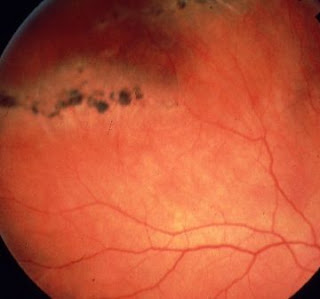

Bleeding into the vitreous cavity can cause floaters and may be caused by diabetes, hypertension, trauma, retinal tears or retinal. Retinal disease/health series, retinal tears. harvard health publications: What you can do about floaters and flashes in the eye. A retinal tear may cause you to notice new floaters, or black spots that pass through your vision, and you may also notice flashes of light. Retinal tears in rhode island. A tear on my left eye was from 1 o'clock to 3 o'clock. I think major issues like floaters and retinal tear occur due to the lack of practice of the doctor and the treatment available by the hospital. Retinal detachment is often accompanied by flashes and floaters in your vision.

Sanjay sharma of queen's university in kingston, ont., and his colleagues found that one in seven patients with either floaters or light flashes has a retinal tear that could lead to. It is imperative that a retinal tear be diagnosed early. A retinal tear can lead to fluid and blood collecting in the eye, which can cause the development of several new floaters and loss of vision if the tear leads to a retinal detachment. American society of retina specialists: Retinal tear (when vitreous detachment tears a hole in the retina). The floaters will not disappear, but they may settle, appearing. Sometimes new floaters can be a sign of a retinal tear or retinal detachment — when the retina gets torn or pulled from its normal. This condition can lead to a retinal detachment when left untreated. What is the treatment for eye floaters? The presence of retinal tears with new onset of floaters was surprisingly high (14%; What you can do about floaters and flashes in the eye. Bleeding into the vitreous cavity can cause floaters and may be caused by diabetes, hypertension, trauma, retinal tears or retinal. A tear on my left eye was from 1 o'clock to 3 o'clock.